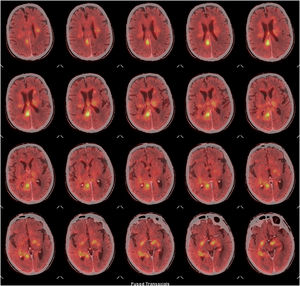

Durante su ingreso en UCI se practicó un fondo de ojo que no detectó la presencia de papiledema. La resonancia magnética (RM) mostró una afectación multifocal confluente bihemisférica de predominio central con extensión mesencefálica izquierda, cuyas características radiológicas sugerían como principal sospecha diagnóstica que se pudiera tratar de un linfoma cerebral (fig. 1B-H). La tomografia computarizada con emisión de positrones (PET/TC) mostró múltiples focos hipermetabólicos encefálicos concordantes con las lesiones descritas en la resonancia magnética y compatibles con un proceso linfoproliferativo de alto grado, SUV (Standarized Uptake Value) máxima de 10,9 (fig. 3). Debido a la situación clínica del paciente no fue posible realizar una biopsia cerebral para la obtención de material histológico.

PET-TC cerebral con 18F-FDG, cortes axiales. Múltiples focos hipermetabólicos en ambos hemiferios afectando a la sustancia blanca subcortical bifrontal, de los centros semiovales, de los núcleos de la base y de la corona radiada, así como la sustancia blanca periventricular, sustancia blanca del lóbulo temporal derecho. Marcado hipermetabolismo en todo el cuerpo calloso, fórnix derecho, comisura blanca anterior, cintas ópticas bilaterales, hipocampo derecho y pedúnculo cerebral izquierdo, la más destacable por su metabolismo localizada en el fórnix derecho. Hallazgos sugestivos de un proceso infiltrativo tumoral (alto grado).